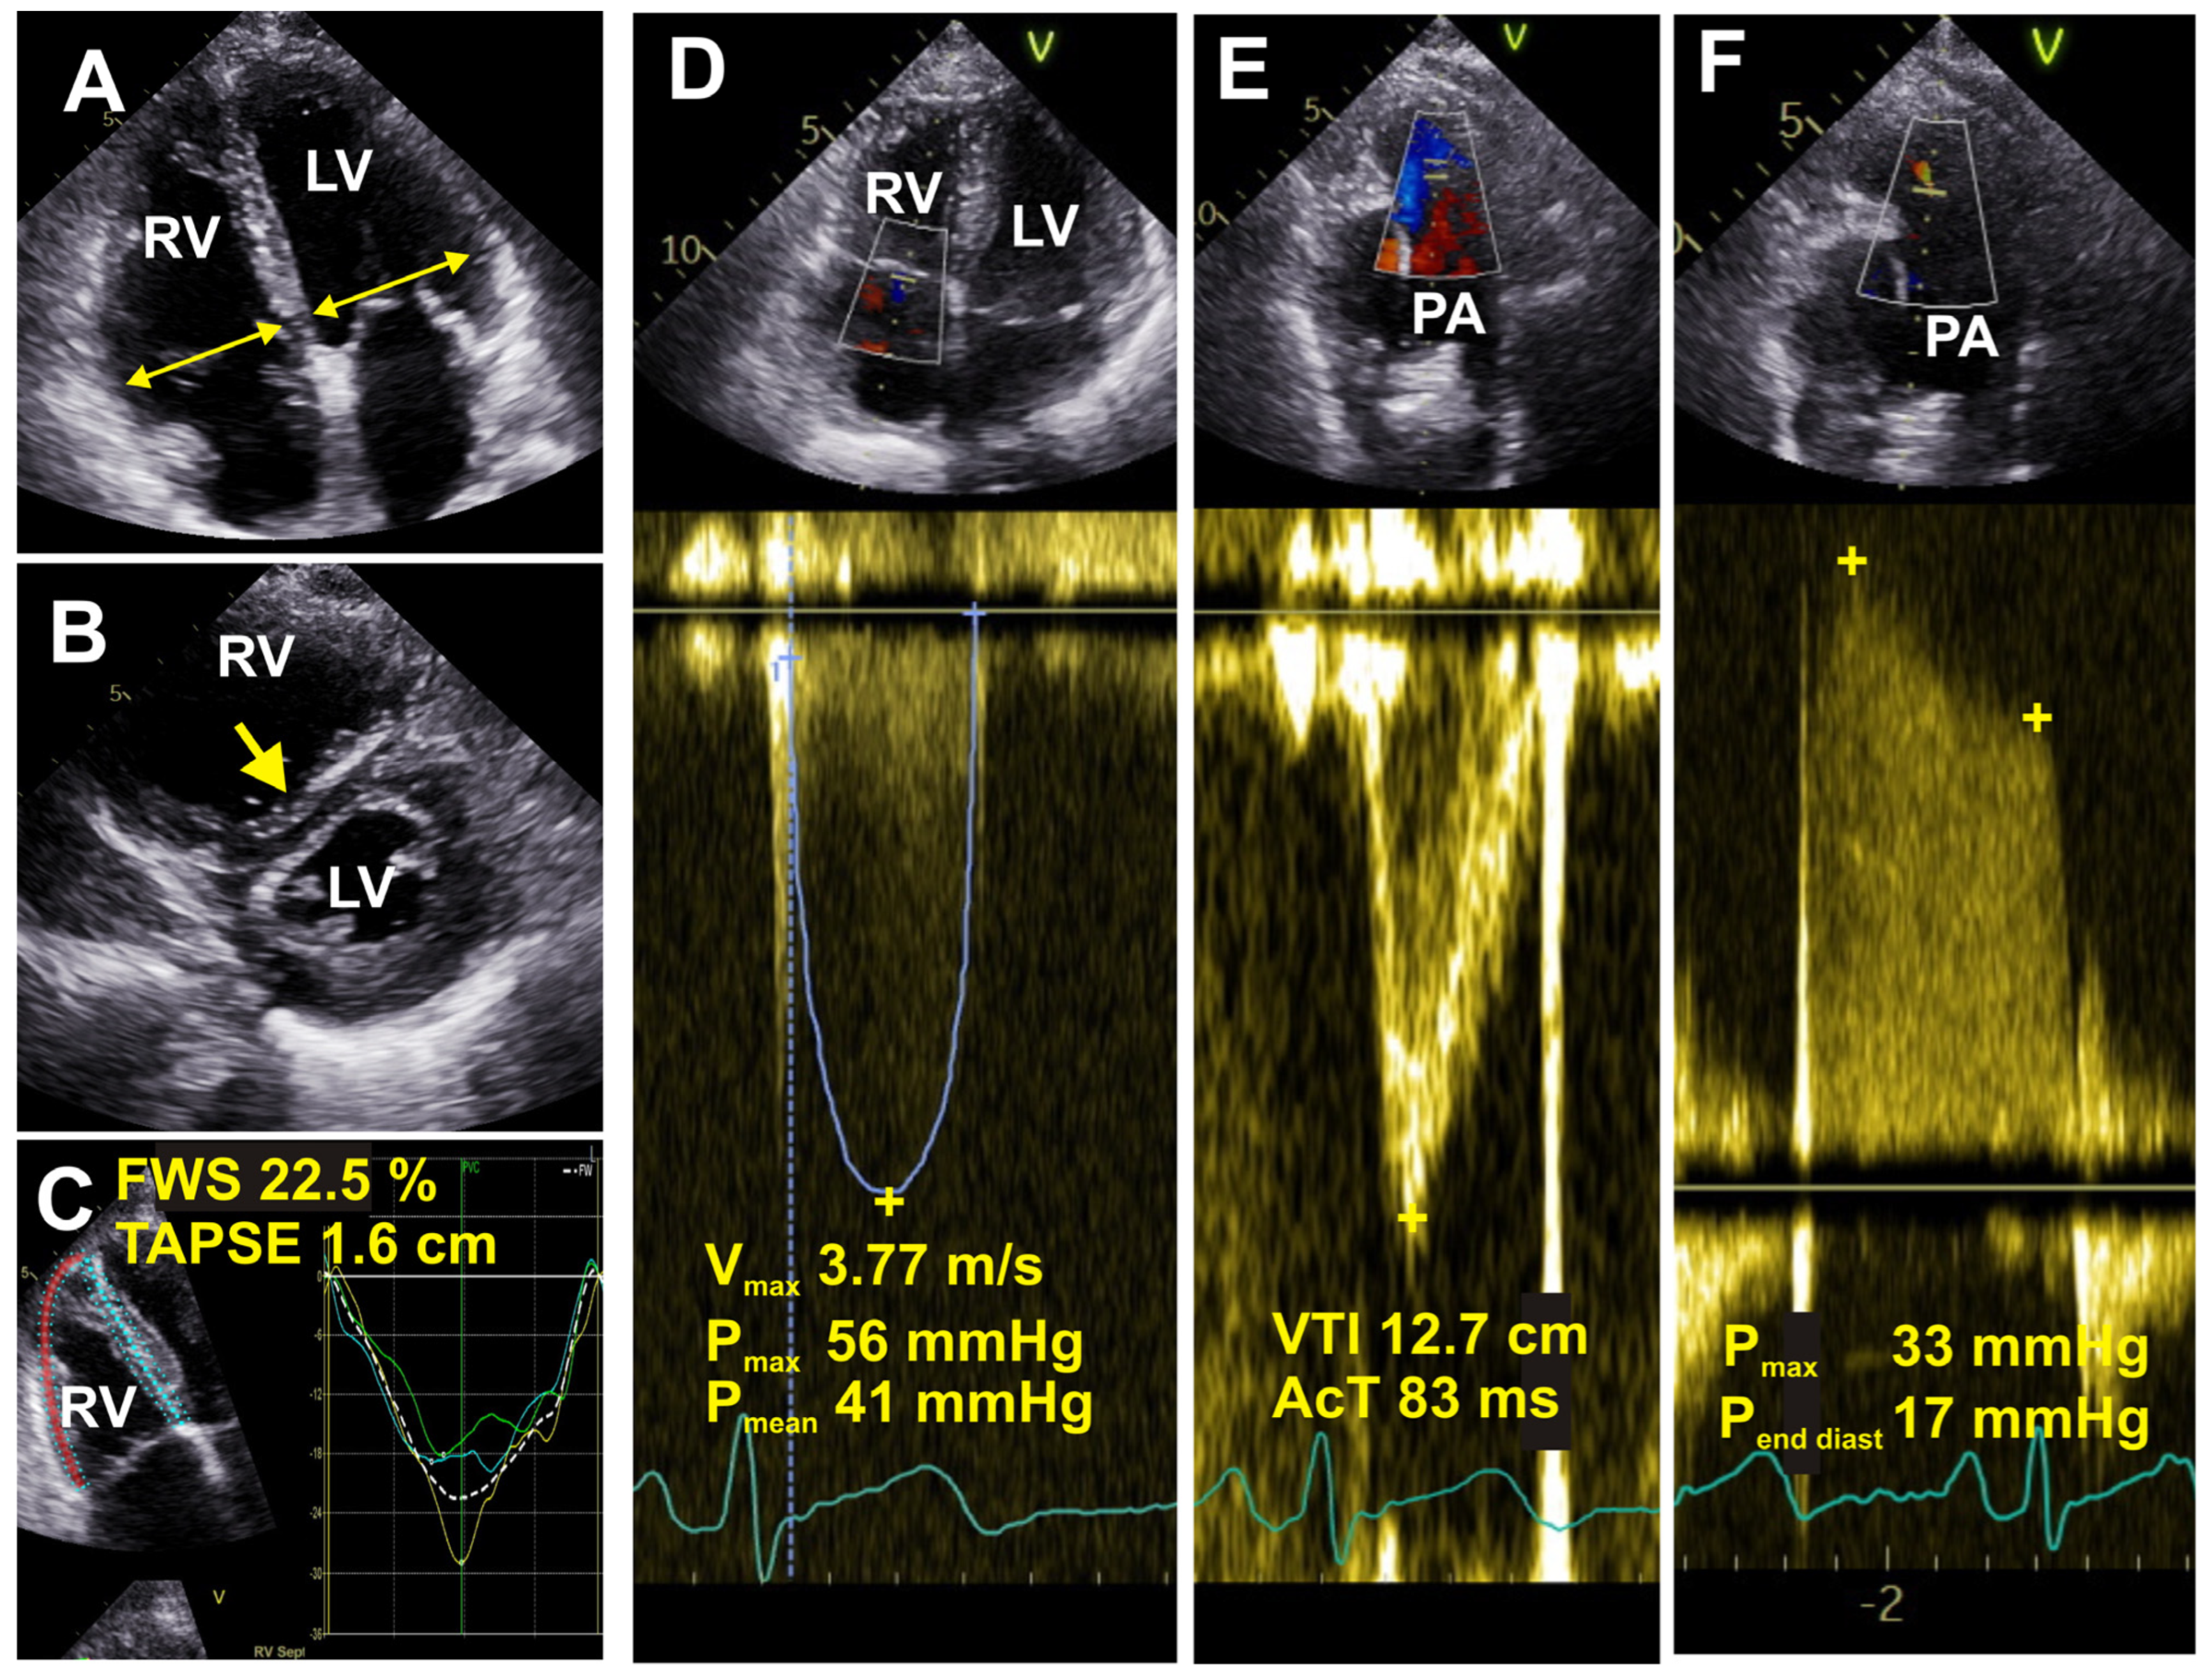

6.5. Echocardiography